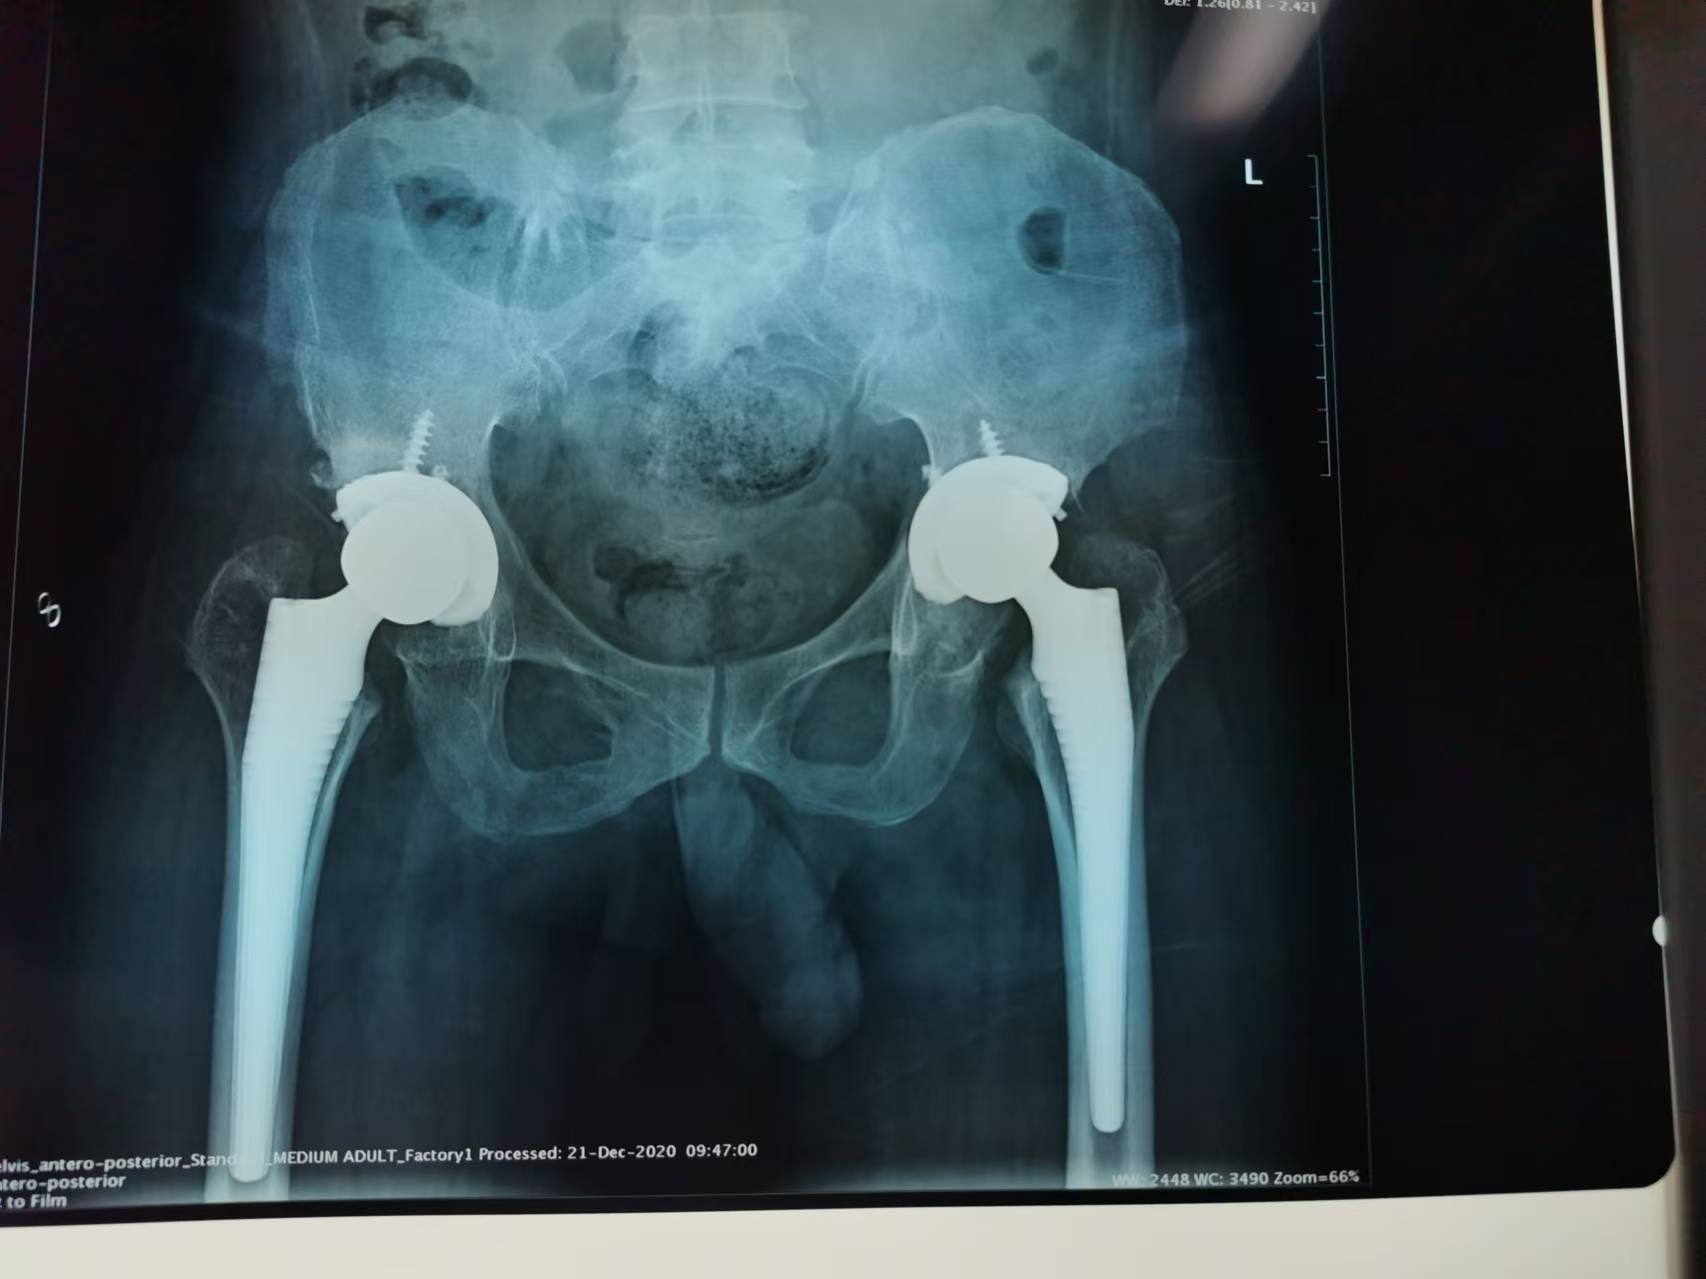

首页 > 张恒云工作室 > 影像资料 二